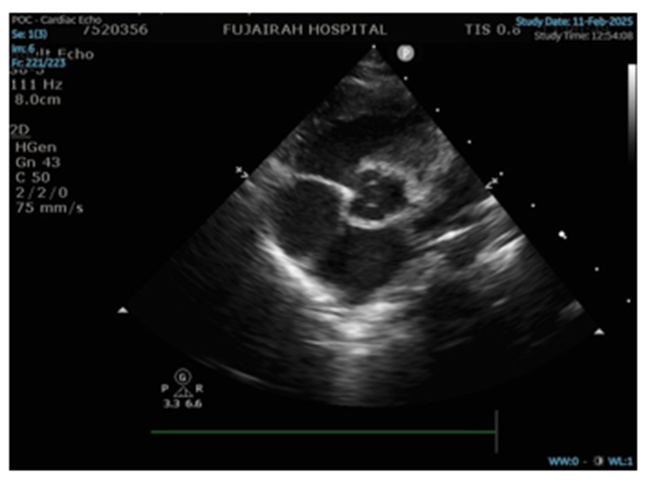

Echocardiography demonstrated progressive dilation of the left atrium and left ventricle with preserved systolic function, suggestive of early dilated cardiomyopathy (Figure 2). The aortic valve was functionally bicuspid (Figure 3). Frequent premature atrial and ventricular contractions were observed, likely secondary to metabolic instability. Medical management included captopril, spironolactone, and hydrochlorothiazide.

Figure 3: Para sternal short axis (PLAX) view reveals functionally bicuspid aortic valve.